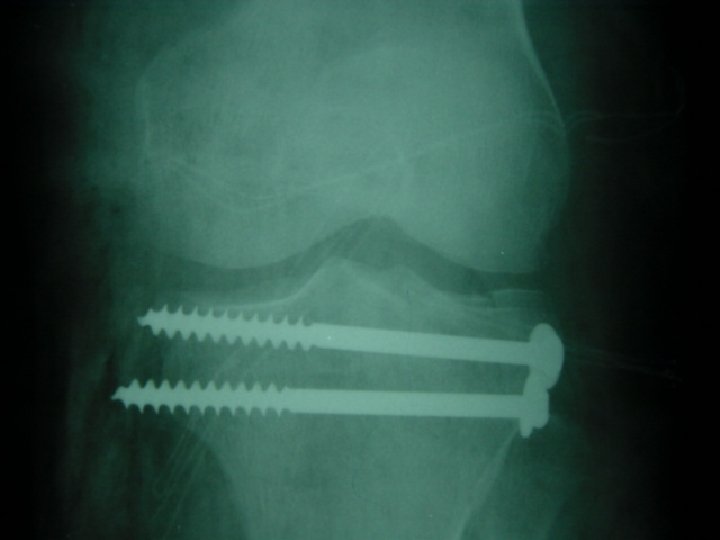

Open reduction 1 -displaced intra articular indications 2 -unstable Fr 3 -avulsion Fr 4

Open reduction 1 -displaced intra articular indications 2 -unstable Fr 3 -avulsion Fr 4 -Displaced pathologic Fr 5 - only operation indication 6 -Salter 3, 4 7 -compartment syn. 8 -NONUNION

Difinitive 1 -DEBRIDMENT 2 -FRACTURE TREATMENT A-INTERNAL FIXATION B-EXTERNAL FIXATION 3 - SKIN